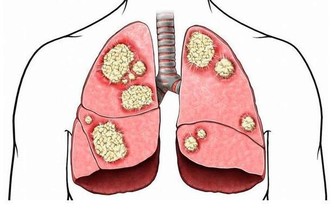

當一定量的內臟脂肪其實是人體必需的,因為內臟脂肪圍繞著人的臟器,對人的內臟起著支撐、穩定和保護的作用。然而,當內臟脂肪堆積過多時,一方面就會形成水桶腰、將軍肚等造成身材不美觀的問題;另一方面,內臟長期堆積過多脂肪會影響消化功能,導致內分泌紊亂,還增加了患高血脂、高血壓、脂肪肝等疾病的機會,下面就跟小編一起詳細瞭解吧!